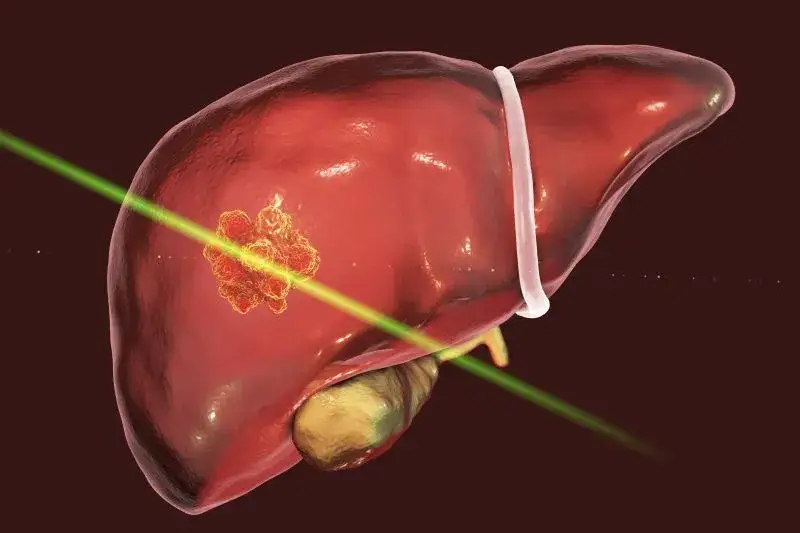

Poznaj najczęstsze objawy nowotworu wątroby i dowiedz się, jakie niepokojące sygnały mogą wskazywać na rozwijającą się chorobę.